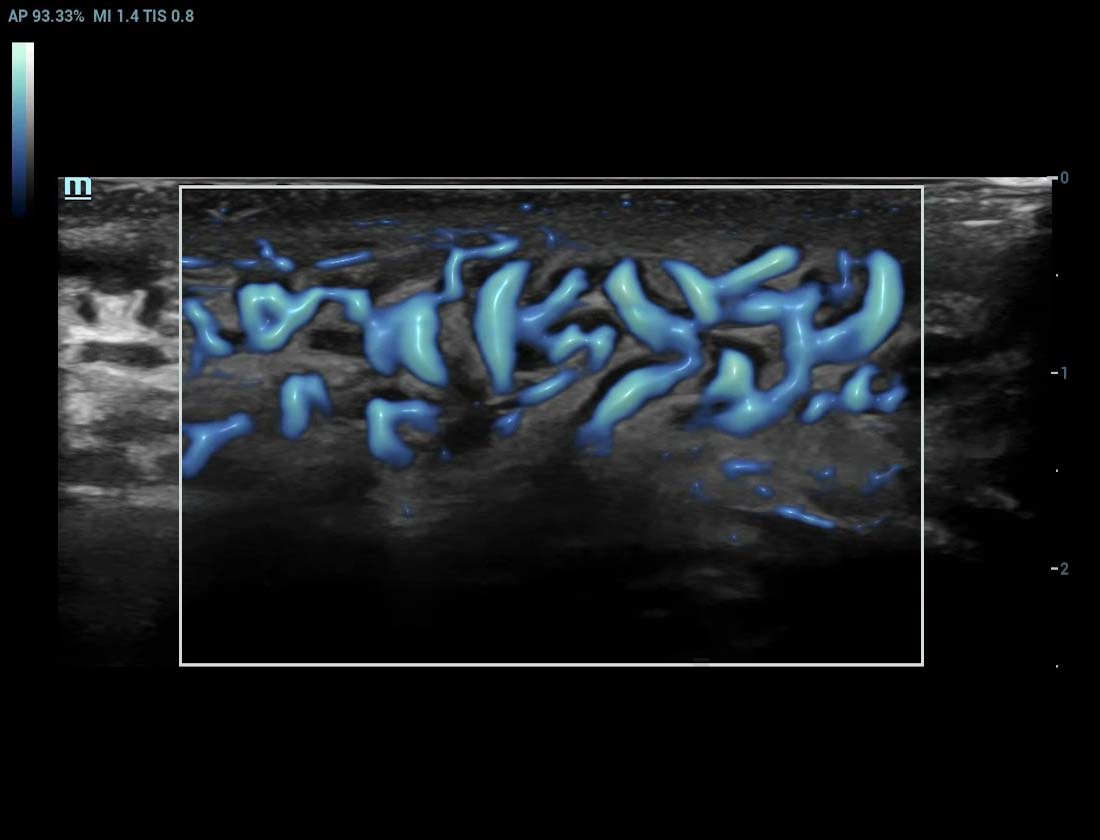

Angiografia ultramicroscû°pica (Ultra Micro Angiography, UMA)

UMA aumenta a confian?a diagnû°stica ao expandir a visibilidade dos fluxos sanguûÙneos atûˋ o nûÙvel de vasos minû¤sculos, com sensibilidade e resolu??o superiores.

sUMA ã Rins

sUMA ã Nû°dulos linfûÀticos

sUMA ã Les?o em MSK